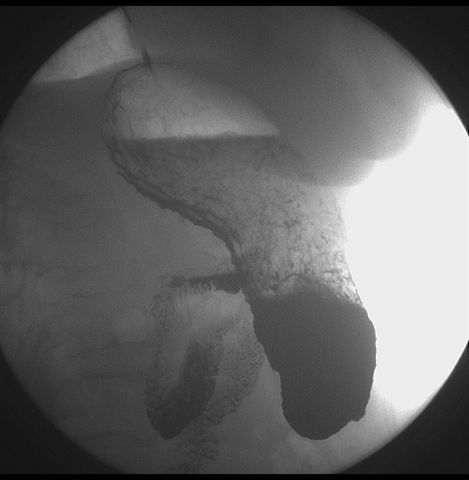

标题: X6872:F,69y,胃部不适。

胃窦至幽门段胃壁僵硬,扩张受限,局部纠集粘破坏,呈杵状。提示溃疡癌变可能性大。

支持考虑胃窦癌可能,胃内滞留液太多,胃窦部僵硬。

瀑布型胃,胃粘膜那是一个乱,窦部充盈不好,第16幅窦部粘膜反倒又很顺,先定个胃炎胃窦炎胃窦癌待排之类,建议进一步作胃镜检查。

胃窦部见钡池影,局部粘膜紊乱,纠集呈杵状改变,胃壁扩张受限,胃窦癌可能性大,建议胃镜检查.

胃窦部管腔扩张度较差,形态略有改变,胃窦粘膜显示欠佳,胃窦部占位可能性大,结合胃镜活检。

胃窦部狭窄、稍僵硬,考虑胃窦癌?建议胃镜检查。

北京肿瘤医院胃镜诊断皮革胃。